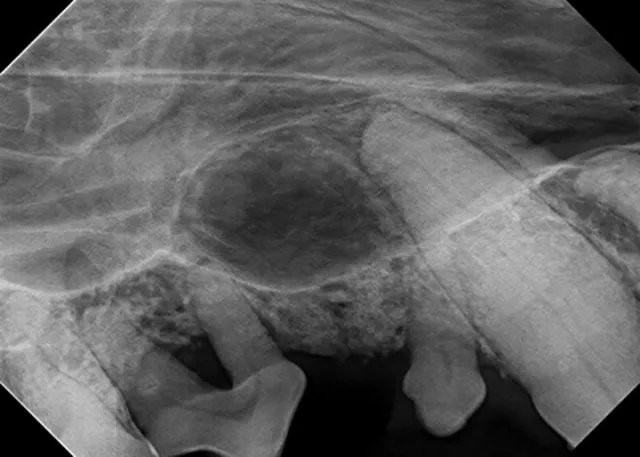

The relatively simple parallel technique is used to image the mandibular caudal cheek teeth on small dogs and cats.

For large dogs, use this technique to image teeth from the third premolar to the last molar. This portion of the oral cavity has room enough to place the sensor parallel and adjacent to the desired teeth, on the lingual aspect of the mandible. Then, aim the tube head perpendicular to the sensor.

For example, image the caudal cheek teeth in the maxilla with the tube head at a 60° angle from the horizon.2 When the patient is positioned with the maxilla parallel to the horizon, the sensor can also be placed parallel to the horizon (ie, inside the oral cavity and adjacent to the desired teeth), making it much easier to visualize the angle.

Place the sensor horizontally inside the oral cavity, with the cusp tip of the desired teeth at the edge of the sensor. Placing the sensor inside the oral cavity will provide enough room to catch the radiograph image.

Radiographs should be taken in the same order each time. Starting with the right maxillary molars, move the sensor and tube head around the entire arch until the left caudal maxilla is reached. Then, position the patient in ventral recumbency and repeat the process, starting with the left mandibular molars. Continue around the arch until the right caudal mandible is reached. This sequence is suggested because full-mouth-series templates included in most digital software programs are arranged in this order and will result in the mirror image for correct viewing of radiographs.